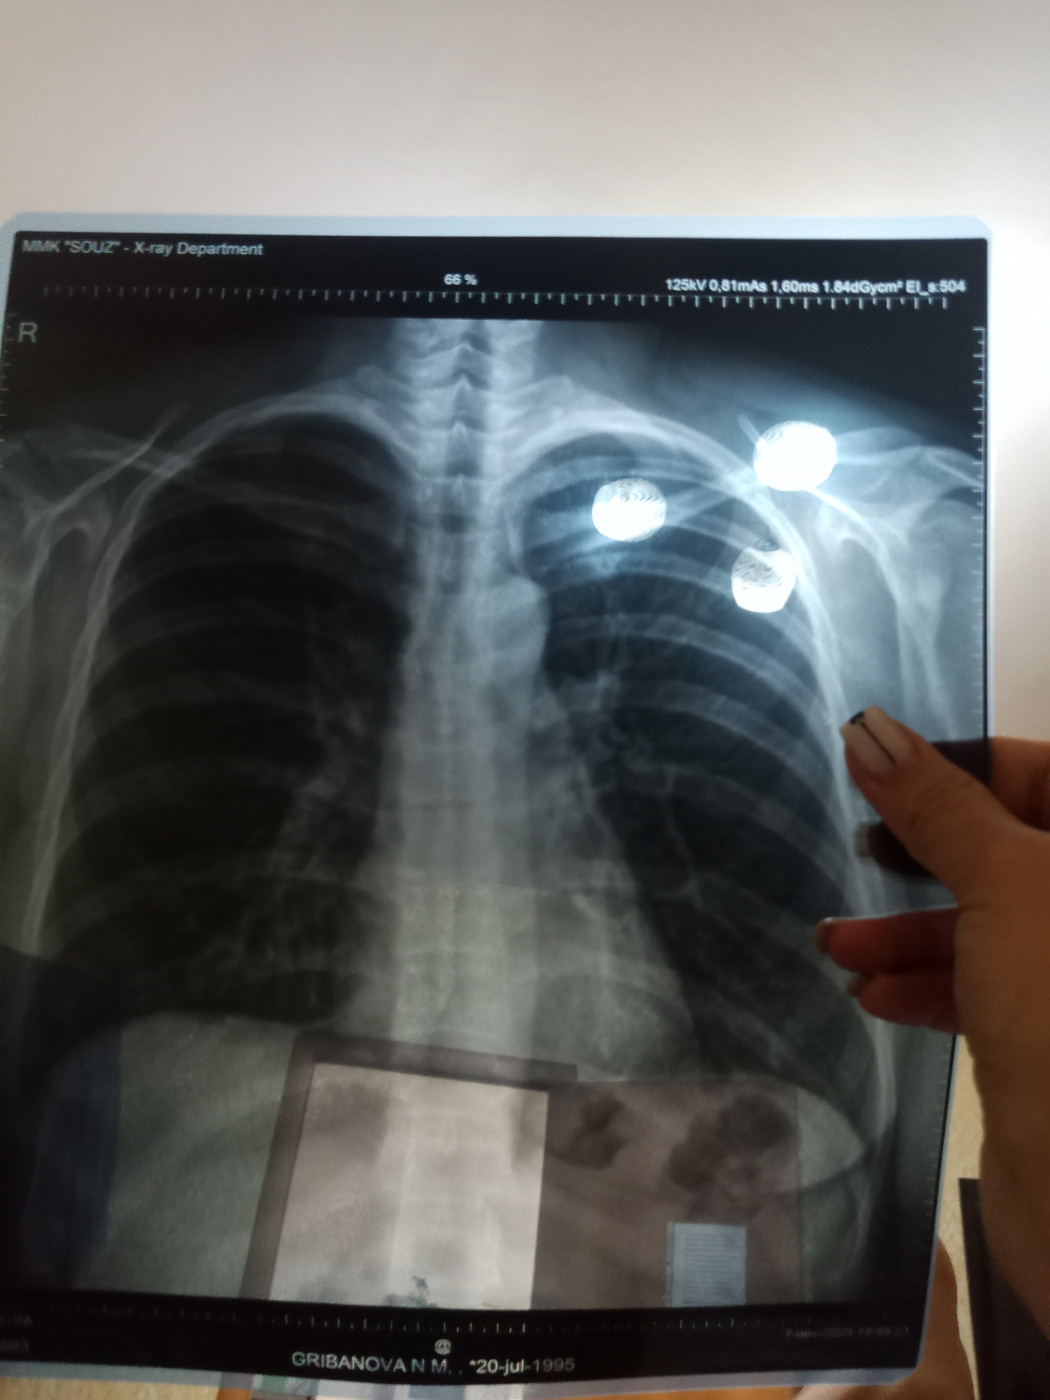

Рентген груди